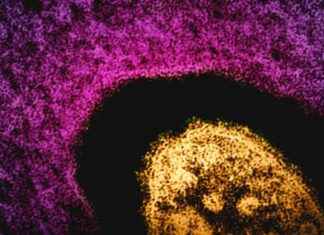

In a small Texas county with alarmingly low vaccination rates, a measles outbreak is on the rise. The story began in late January when two school-age children from Gaines County were admitted to the...

Tragedy Strikes: Measles Claims Life of Unvaccinated Adult in New MexicoIn a devastating turn of events, state health officials in New Mexico revealed on Thursday that an adult who had contracted measles has tragically...